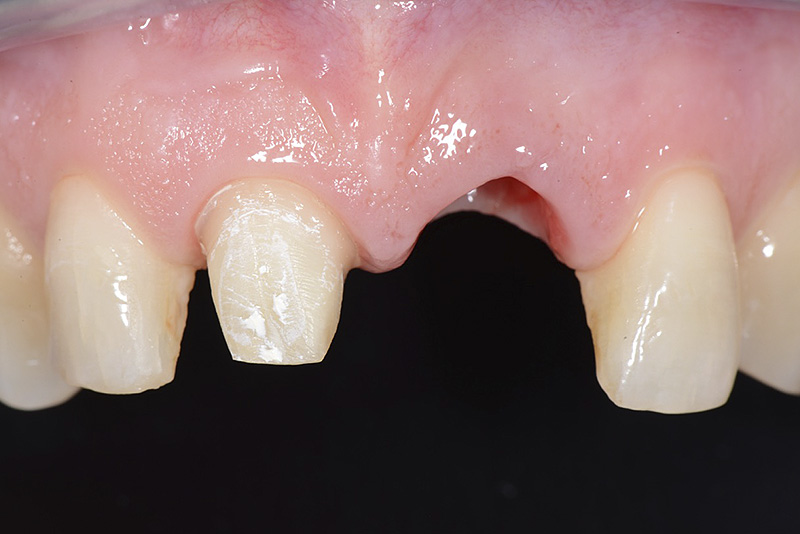

PREMESSA: in seguito all’estrazione dell’incisivo laterale superiore di destra, resasi necessaria per cause batteriche, si decide di affrontare il caso con il posizionamento di un impianto in sostituzione dell’elemento mancante dopo guarigione del sito infetto. Con tecniche rigenerative sia dei tessuti ossei mancanti a causa dell’infezione pregressa, sia dei tessuti gengivali che appaiono inizialmente troppo spostati in alto, si ripristina una corretta morfologia delle parabole (contorni) gengivali e delle papille interdentali (triangoli di gengiva tra due denti vicini).

Vengono utilizzati 2 tipi di provvisori: il primo, cementato ai denti vicini, viene utilizzato dal momento dell’estrazione del dente fino ad impianto osteointegrato (circa 6 mesi); il secondo, avvitato direttamente all’impianto, ha una funzione di prova estetica ma soprattutto di guida per la maturazione dei tessuti gengivali peri-implantari portandoli verso la maturazione completa prima di posizionare la corona finale in disilicato di litio.